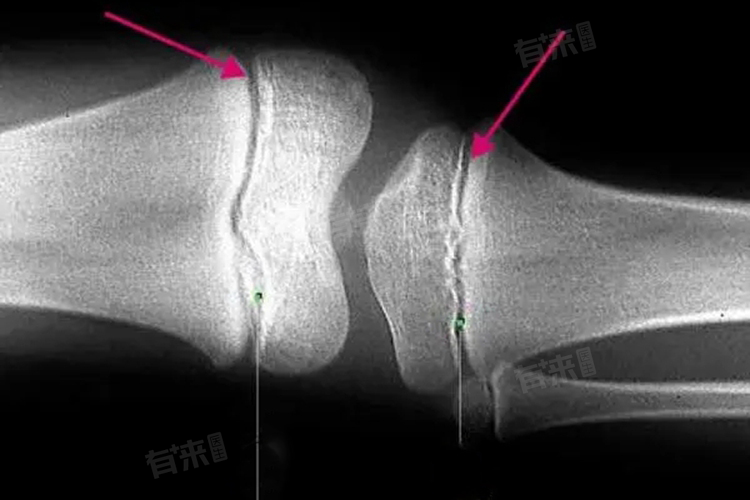

- 一旦骨骺线闭合,骨骼的生长潜力就基本耗尽。此时,无论进行何种运动,包括打篮球,都无法再促进骨骼的生长和身高的增加。因为骨骺软骨已经与周围的骨骼发生融合,无法通过骨骺形成新的骨骼组织。